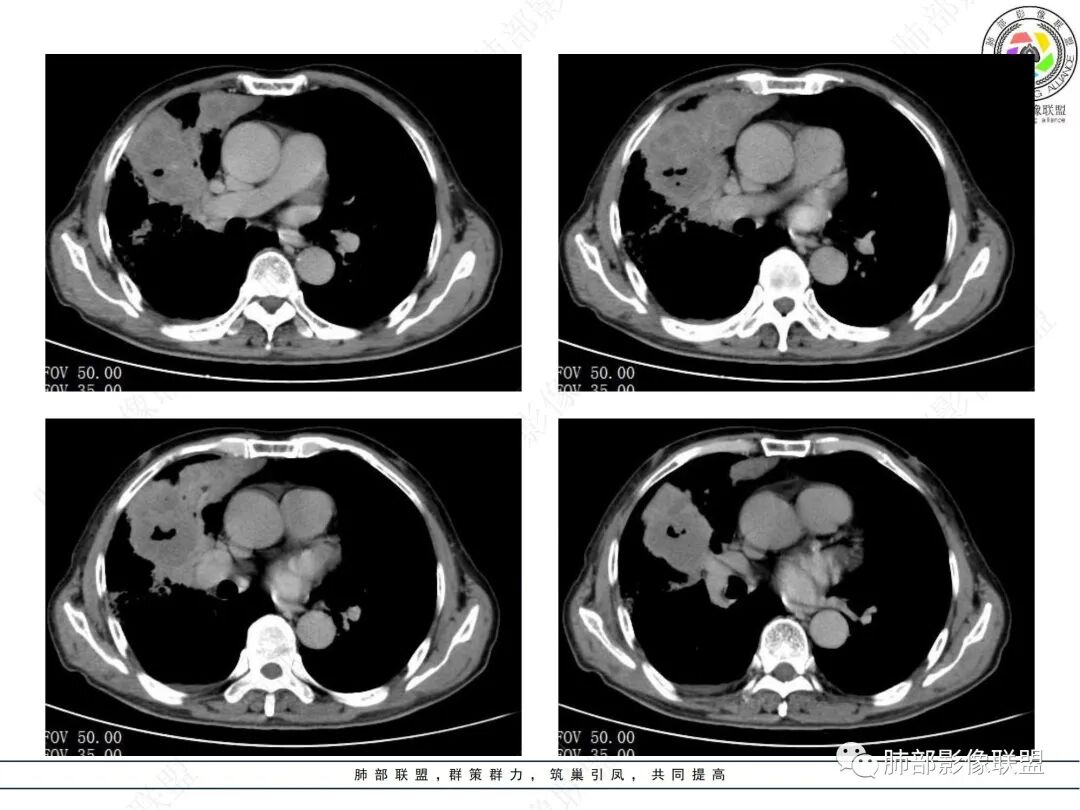

病例资料

右肺上叶实变,宽基底与胸膜相连,邻近胸膜积液,上叶支气管阻塞,不均匀强化,血管显示可,局部坏死环形强化,可见气泡,考虑慢性炎症伴脓肿,放线菌?鉴别腺癌

右肺上叶尖段大片状实变,近肺门侧支气管闭塞,并可见病灶内部有片状液化坏死区,有空泡气体,病灶紧贴胸膜,胸膜反应性增厚,伴有少见积液,增强扫描内部不均匀强化,血管走形正常。影像符合慢性化脓性感染。

右肺上叶大片实变影,内密度不均匀,可见坏死环形强化,支气管被粘液栓阻塞,首先考虑感染性病变,奴卡?放线菌感染?

右肺上叶大片实变,密度不均,近端环形强化并见空泡,病灶与胸膜广基相连,之间并可见积液,考虑放线菌,鉴别腺癌

晨读:右肺上叶实变,密度欠均匀,不均匀强化,内血管走形可,近端环形强化并见空泡,考虑放线菌可能,鉴别腺癌

右肺上叶实变,宽基底与胸膜相连,不均匀强化,血管显示可,局部坏死环形强化,可见气泡,考虑慢性炎症伴脓肿,放线菌?鉴别腺癌

老年女性患者胸痛咳嗽半年多时间。右肺上叶大片状实性病灶,近端支气管受压变窄。病灶内部密度不均,伴有不均匀强化,有局灶坏死,以及有支气管造影征,胸膜面显示不行,伴有少量的积液,病灶有局部的膨胀,纵隔淋巴结增大。

老年女性患者胸痛咳嗽半年多时间。右肺上叶大片状实性病灶,近端支气管受压变窄。病灶内部密度不均,伴有不均匀强化,有局灶坏死,以及有支气管造影征,胸膜面显示不清,伴有少量的积液,病灶有局部的膨胀,纵隔淋巴结增大。

晨读,中年女性,咳嗽半年,右肺上叶斑片影,可见坏死及环形强化,血管影走形自然,胸膜增厚积液,纵隔淋巴结增大,右肺上叶支气管阻塞,考虑慢性炎症伴局部脓肿形成,鉴别腺癌?淋巴瘤?

中年女性,咳嗽,咳痰半年,CRP升高,右肺上叶大片实变,密度不均匀,边缘部见类圆形低密度影,内夹杂气体影,增强后呈环形强化,病变内血管走形征象,边缘略毛糙,考虑①炎性伴脓肿形成②上叶支气管截断,恶性不除外,鳞癌?

右肺门结节,显著强化,内可见坏死及悬浮气泡,远端阻塞性肺不张,心脏纵隔右移,结节及不张内血管影走行自然,并可见粘液拴,隆突下淋巴结肿大,慢性病程,病变跨叶,首选感染性病变放线菌感染,其次鉴别腺癌

晨读:右肺上叶大片状实变影,血管走形自然,可见类圆形低密度区,其内可见气泡影,纵膈内可见肿大淋巴结显示。考虑慢性炎症并脓肿形成,放线菌可能。鉴别淋巴瘤、腺癌。